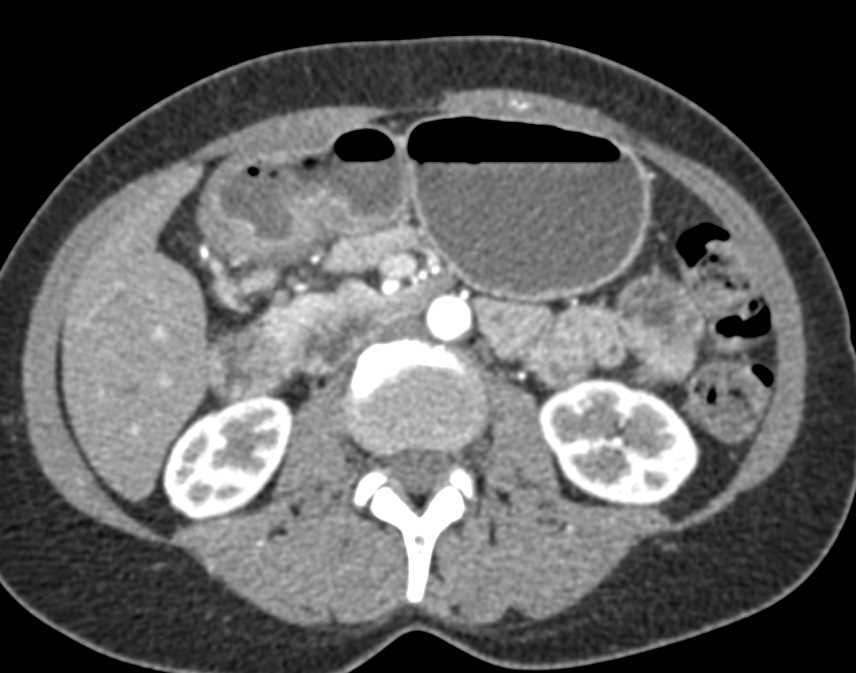

Diagnosis

Pills in the Stomach